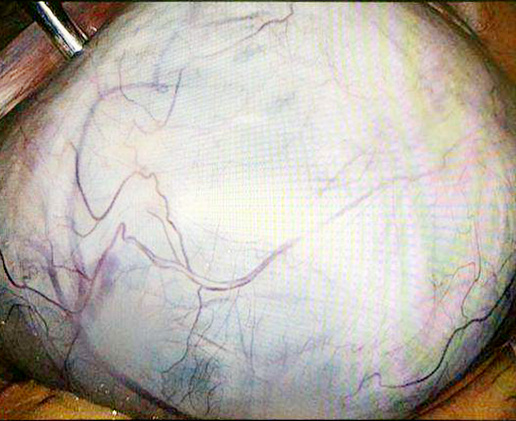

婦科主任艾永航專家團隊為李奶奶制定了科學(xué)的治療方案,在與患者及家屬充分溝通之后,李奶奶家屬簽下了手術(shù)同意書。于2019年6月13日采用“全麻下行腹腔鏡探查術(shù)”,手術(shù)時間約一個小時。手術(shù)過程很順利,術(shù)中在李奶奶腹部取出一個巨大盆腔包塊。手術(shù)結(jié)束后,李奶奶家屬在手術(shù)間門口焦急而耐心的等候,當(dāng)家屬看見如此巨大的盆腔包塊時候,流下了心疼而欣慰的淚水。

▲ 腹 腔 鏡

婦科艾永航主任運用嫻熟的腔鏡技術(shù)和豐富的腔鏡臨床技巧和經(jīng)驗,順利完成了本次腹腔鏡探查術(shù)。艾永航主任表示:如此巨大的盆腔包塊在醫(yī)學(xué)教科書上屬于禁忌癥,這在以往需要采用開腹手術(shù)完成,但是開腹手術(shù)具有切口長、患者痛苦大、住院時間長、恢復(fù)慢的缺點。而采用此次腹腔鏡下的微創(chuàng)手術(shù),只需要通過打三個不到兩公分的小孔就可以順利完成,大大降低了手術(shù)的風(fēng)險,患者八小時就可以下床活動、飲水、食流質(zhì)飲食,三天之后就可以出院。